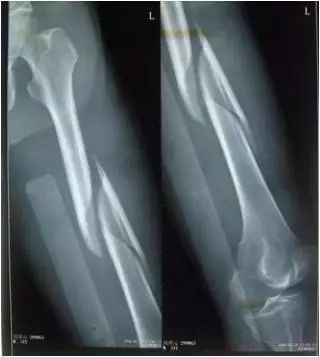

4.骨折

处置:找一个坚硬的外物固定支撑骨折两端。

原因:骨折断端可能会非常锋利,如果没有妥善固定,在搬运时会损伤周围软组织。

作用:固定骨折端,防止二次损伤。